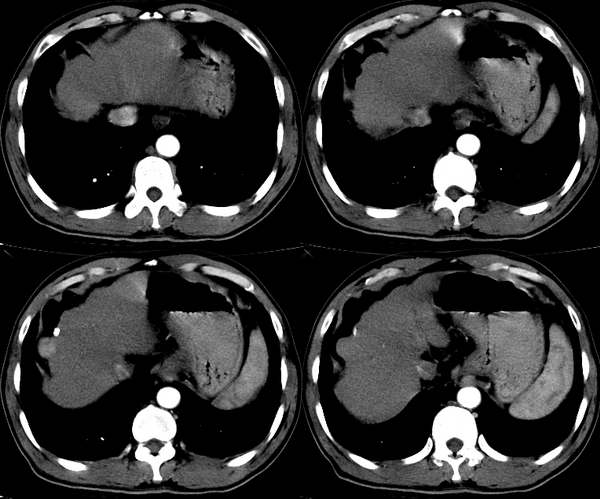

患者 男性 53岁,丙肝病史10年,右上腹隐痛2年,近15天加重,彩超发现肝内实质性肿物,行ct结果肝硬化癌变比较典型,故上传,共同学习。

典型,平扫肝右叶凸向表面等密度结节,动脉期明显强化表现高密度,门脉期稍低密度,延迟低密度

肝脏体积明显缩小,表面呈波浪样改变,平扫肝右叶等密度结节,动脉期明显强化,门脉期及延时扫描病灶呈低密度.典型病例.

典型小肝癌:肝硬化、结节三期强化符合快进快出特点。

肝脏体积明显缩小,表面呈波浪样改变,平扫肝右叶等密度结节,动脉期明显强化,门脉期及延时扫描病灶呈低密度.典型病例.[肝硬化,肝癌]